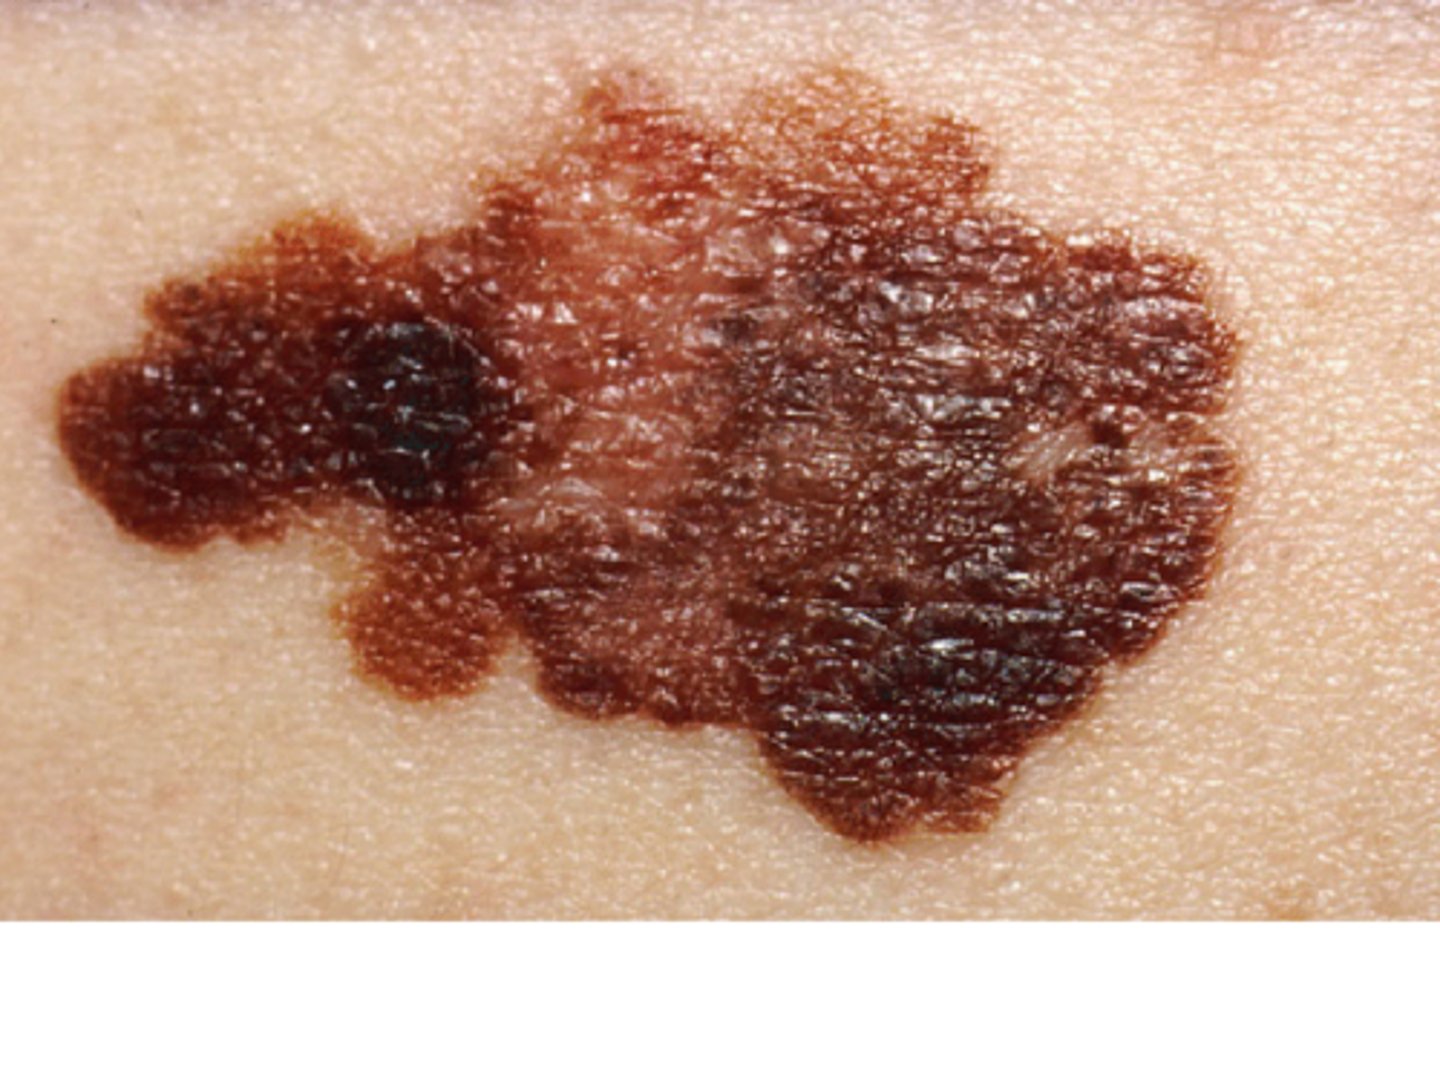

Melanoma

most aggressive/fast growing

least common

often fetal

Red flags of malignancy

Asymmetrical sides

Border has indentations

Color is black/brown/tan

Diameter larger than 6mm

Elevation